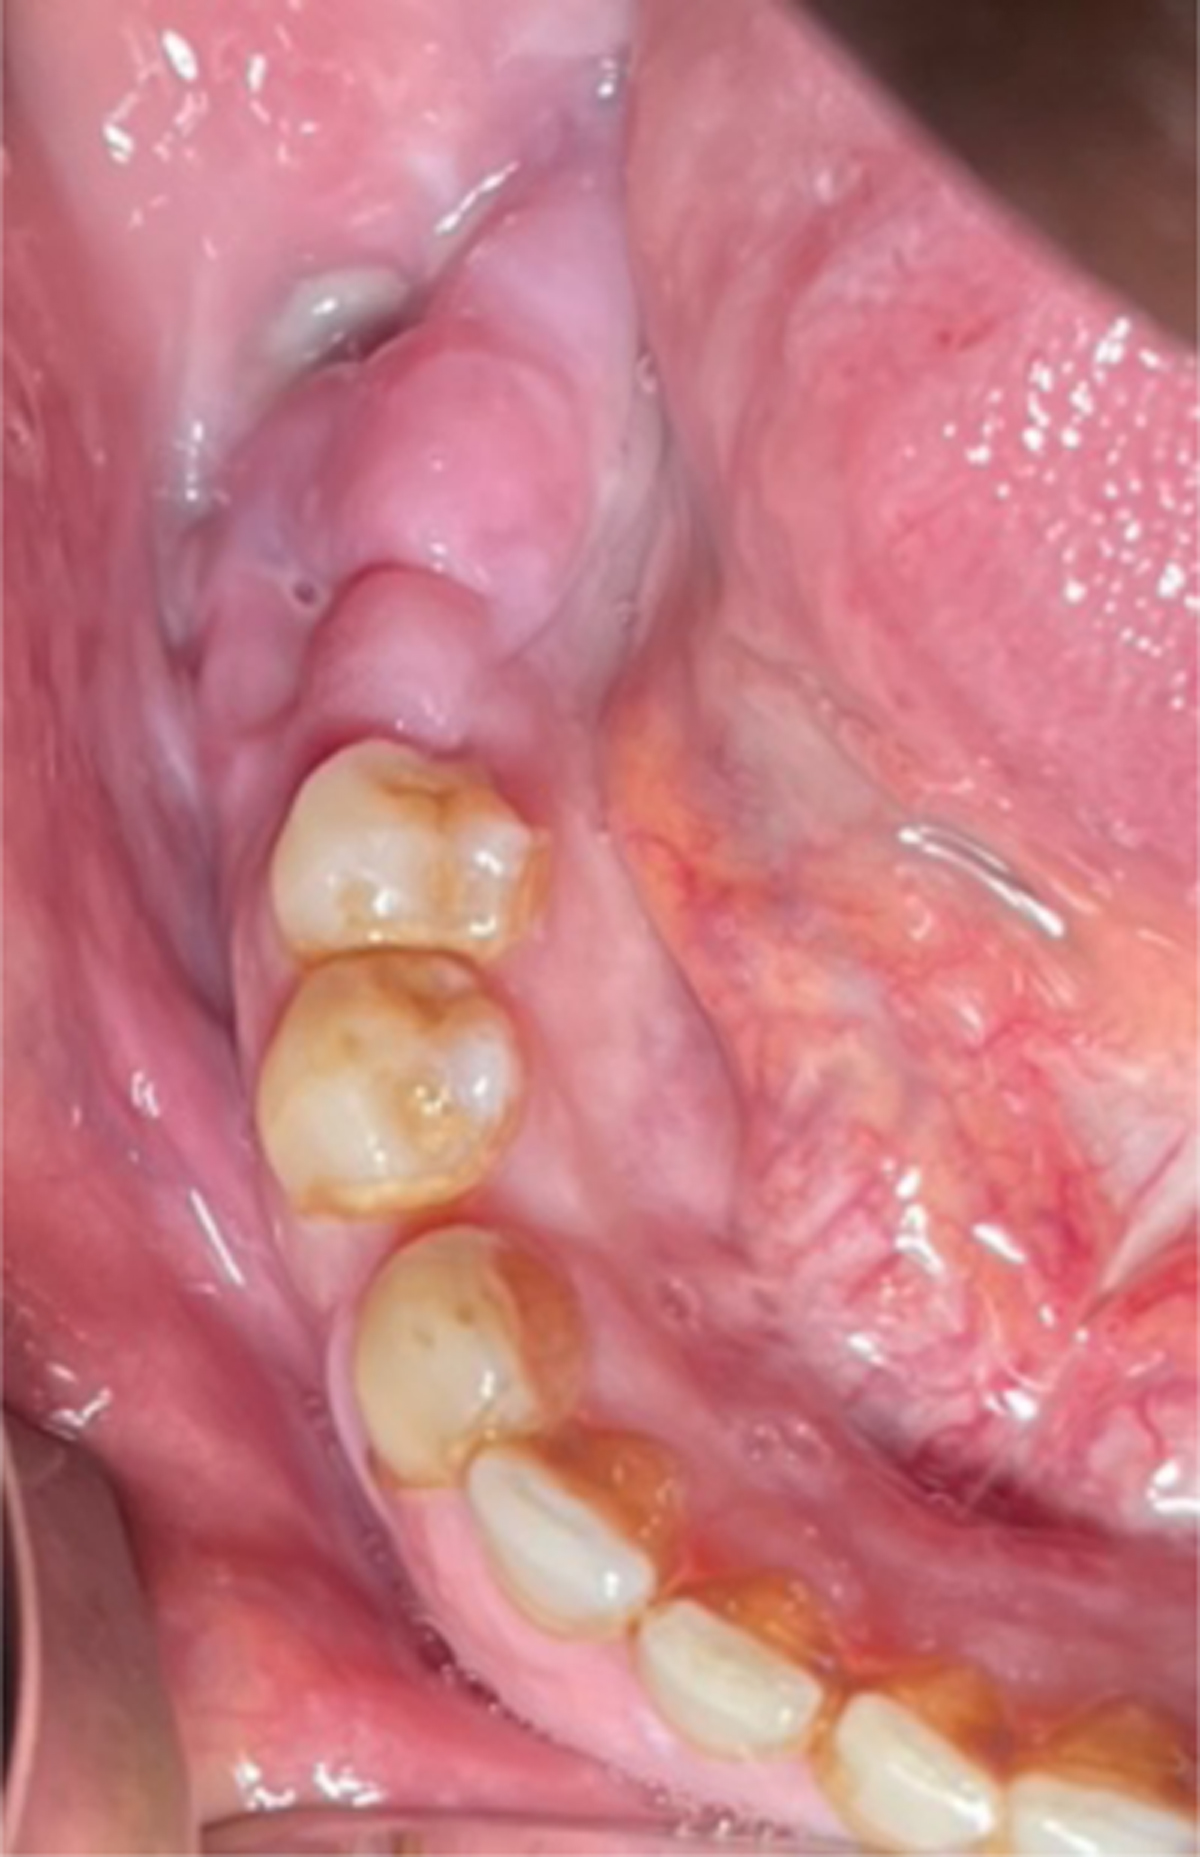

Intraoral view showing swelling and purulent discharge in the right posterior mandible.